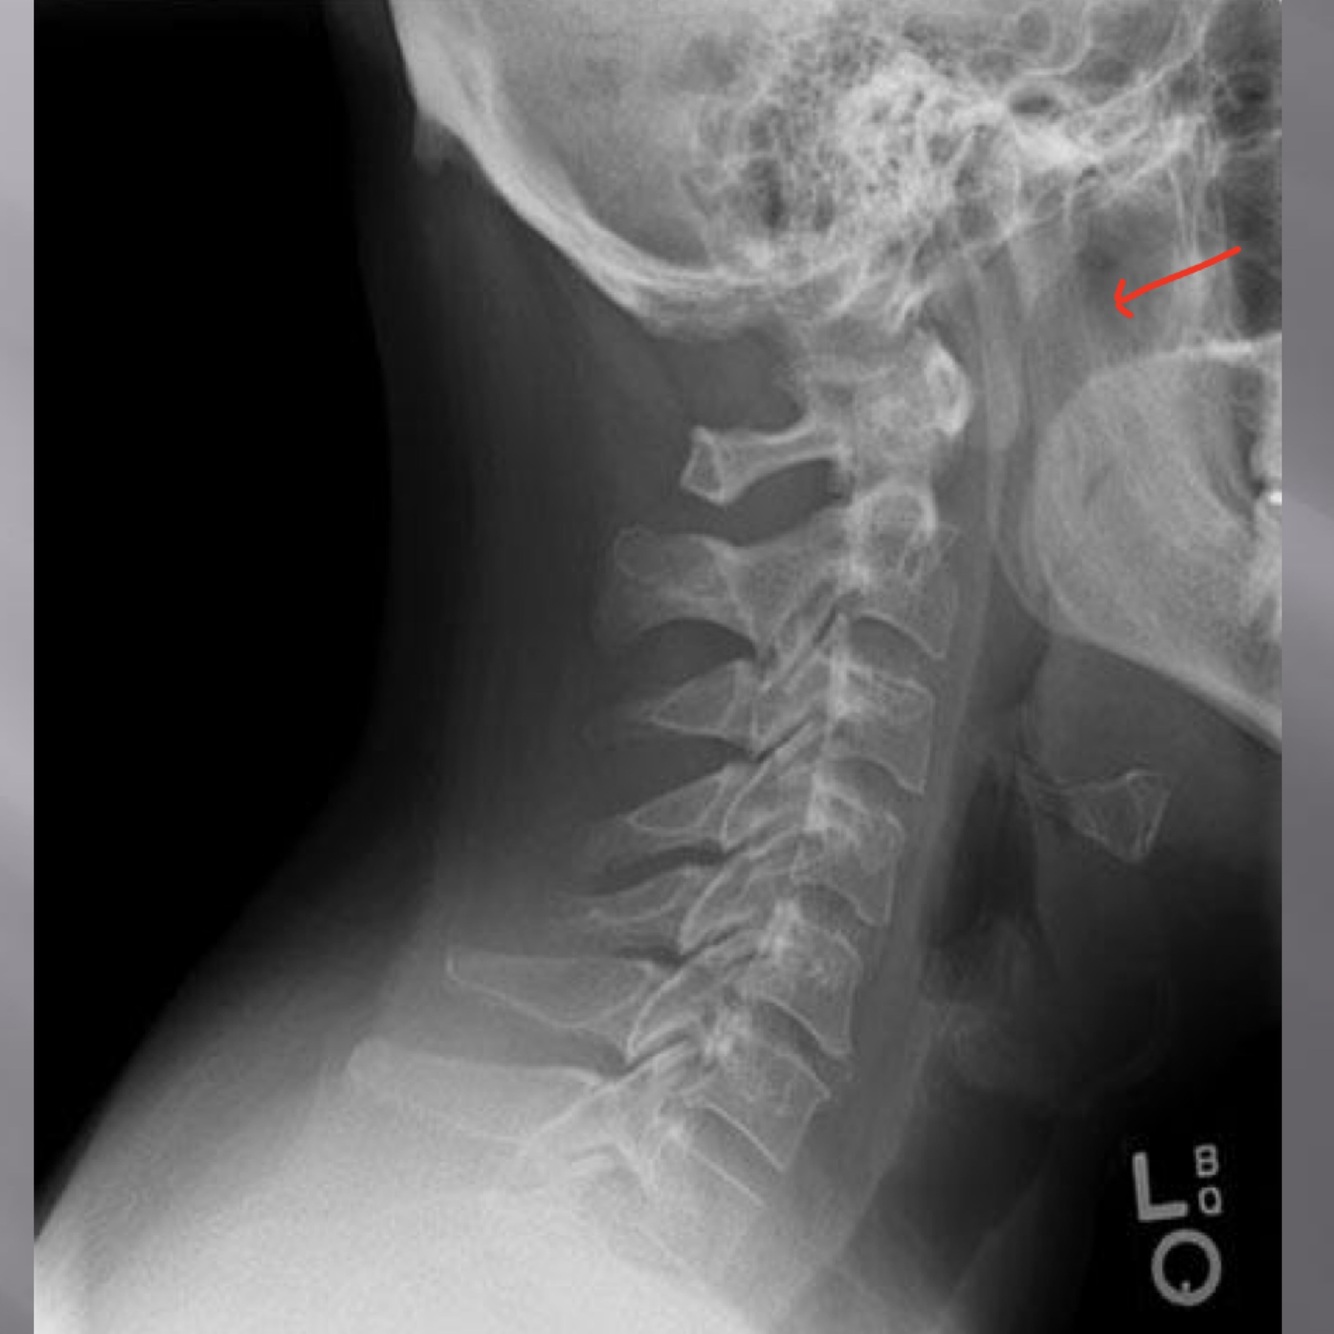

LATERAL CERVICAL LANDMARKS lateral cervical view

external acoustic meatus

Lateral cervical view

mastoid process (air cells)

posterior tubercle of c1

angle of mandible

EOP

spinous process C2-C7

A

sella turcica

dens

posterior arch of C1

Q

lamina c2-c7

uncovertebral joints (joints of luschka)

13

14

rami of mandible

articular processes

Lateral thoracic view

transverse process of c2-c7

19

zygapophyseal joints

22